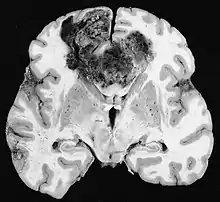

Glioblastome

Les tumeurs des cellules gliales les plus courantes et les plus malignes sont les glioblastomes. Ils consistent en une masse hétérogène de cellules d'astrocytome peu différenciées principalement chez l'adulte. Ils surviennent généralement dans les hémisphères cérébraux, plus rarement dans le tronc cérébral ou la moelle épinière. Sauf dans de très rares cas, comme toutes les tumeurs cérébrales, elles ne s'étendent pas au-delà des structures du système nerveux central.

Le glioblastome peut provenir d'une forme diffuse (II. grade) ou un astrocytome anaplasique (III. grade) développer. Dans ce dernier cas, il est dit secondaire. Cependant, lorsqu'elle survient sans antécédent ni signe de malignité antérieure, on parle de maladie primaire. Les glioblastomes sont traités par chirurgie, radiothérapie et chimiothérapie. Ils sont difficiles à guérir et rares sont les cas qui survivent au-delà de trois ans.

Sur-L'IRM montre une tumeur intracrânienne comme une lésion massive qui peut devenir plus luminescente après utilisation du produit de contraste. Cependant, il y a toujours une anomalie de signal dans -L'imagerie par résonance magnétique, qui indique la présence d'une néoplasie ou d'un œdème vasogénique. Habituellement, une luminescence accrue (amélioration du contraste) indique une tumeur d'un grade supérieur de malignité. Un anneau de contraste est caractéristique du glioblastome, avec la partie luminescente correspondant à la partie vitale de la tumeur maligne, et la plus foncée - zone hypointense correspondant à une nécrose tissulaire.

Dans le tissu tumoral, en général, la plus grande proportion d'amélioration du contraste est due à la barrière hémato-tumorale particulière qui permet le passage de l'iode (CT) et du gadolinium (IRM) dans l'espace interstitiel extravasculaire intratumoral. Cela augmente le signal (densité ou intensité) de la tumeur. Cependant, des précautions doivent être prises pour s'assurer que l'amélioration du contraste ne différencie pas définitivement la néoplasie de l'œdème péri-lésionnel. En fait, la découverte anatomo-pathologique dans le tissu tumoral infiltrant malin du gliome, comme dans le glioblastome et l'astrocytome anaplasique, montre également au-delà de l'œdème vasogénique causé par la destruction de la barrière hémato-encéphalique par la tumeur. Cette dernière condition clinique est difficilement détectable par imagerie diagnostique.